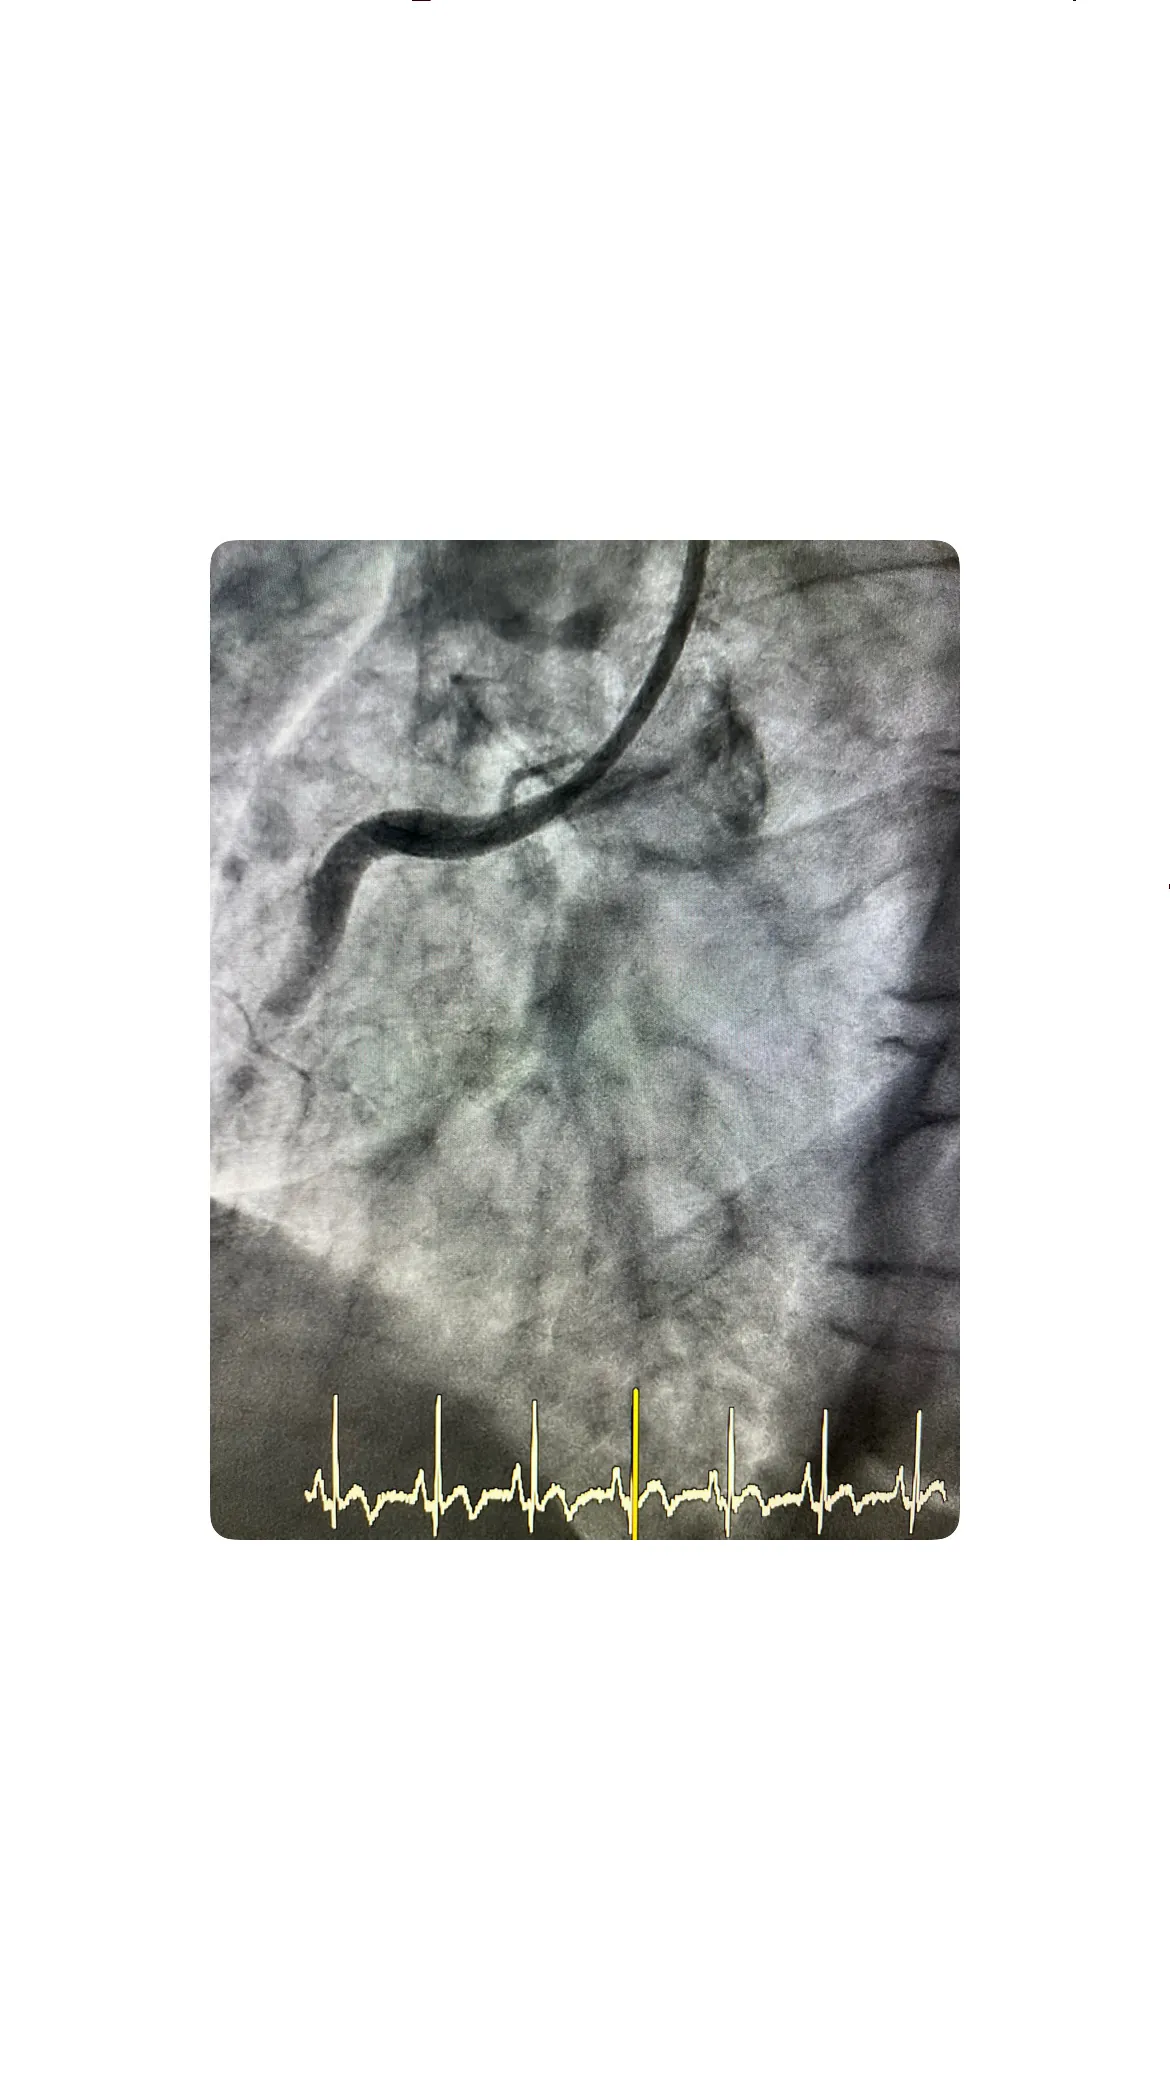

Acceso radial derecho y hallazgo de oclusión

El acceso radial derecho se realiza tras confirmar un buen pulso y preparar el campo estéril, introduciendo el introductor de forma cuidadosa para evitar espasmos o complicaciones locales. Una vez dentro del sistema arterial, se avanza el catéter hasta las coronarias y se inyecta contraste para visualizar el árbol coronario, observándose claramente la oclusión en la arteria responsable del territorio inferior. Este hallazgo explica tanto el dolor torácico como la elevación del ST en las derivaciones inferiores, y marca el punto de partida para la intervención terapéutica dirigida a restaurar el flujo.

Paso de guía, aspiración de trombo y predilatación con balón

Tras identificar la oclusión, se procede a pasar una guía a través de la lesión, maniobra que requiere precisión para atravesar el segmento trombótico sin provocar disecciones ni complicaciones adicionales. Una vez la guía está bien posicionada, se realiza aspiración del trombo, técnica que en este caso resulta efectiva, logrando retirar material trombótico y mejorar parcialmente el flujo. Posteriormente se lleva a cabo la predilatación con balones, inflándolos en el punto de la lesión para abrir la arteria y preparar el lecho vascular, de modo que el stent pueda expandirse correctamente y asegurar una revascularización óptima.